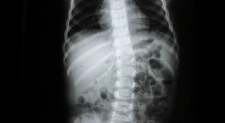

Skolyozun tanısı genellikle fizik muayene ve görüntüleme yöntemleri ile konulur.

• Fizik muayene sırasında doktor, omurganın görünümünü değerlendirir ve belirtileri inceler.

• X-ray, skolyozun derecesini belirlemek için en yaygın kullanılan görüntüleme yöntemidir.

• Gerekirse, MRI veya CT taramaları ile daha detaylı bilgi edinilebilir.

Bu yöntemler, skolyozun ciddiyetini ve tedavi gereksinimlerini belirlemede kritik öneme sahiptir.